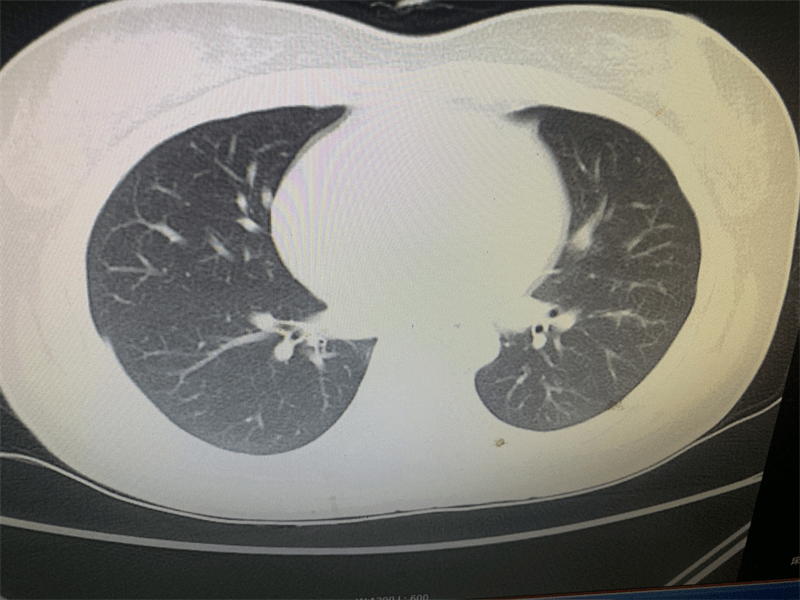

该名女性患者30岁 , 误服“敌草快”后出现消化道出血、血小板减少、肝功能损害、胸腔积液等症状 , 经我院120收治入科 , 急危重症医学部急诊病区副主任李辉立即组织人员进行抢救 , 插胃管洗胃、导泄、血液灌流 , 对症治疗 , 防治并发症 , 防治出现肺纤维化 , 生命体征得到稳定 。 经过连续3天的血液净化 , 患者肝肾功能逐渐得到恢复 , 小便量每日3000ml以上 , 治疗1周后患者病情逐步恢复稳定 。

文章图片